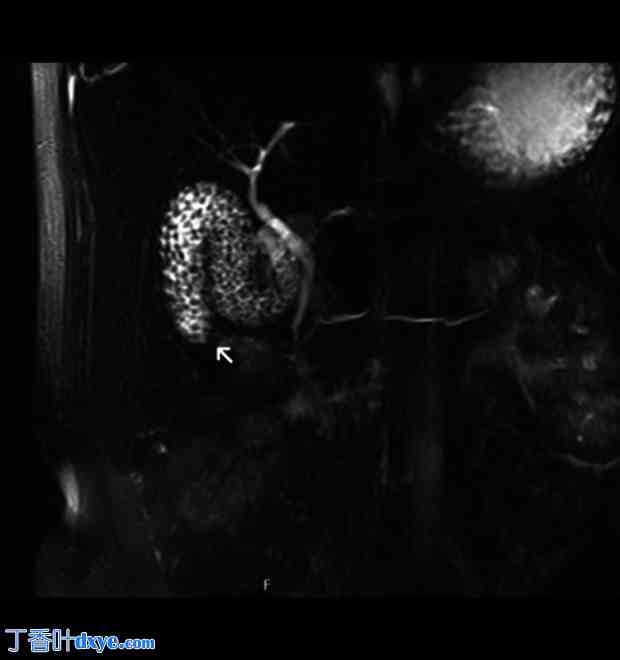

一名 42 岁女性因急性胰腺炎入院。她既往病史包括小肠切除术、子宫切除术及附件切除术、肠系膜淋巴结切除术、阑尾切除术和因神经内分泌肿瘤 (NET) 而进行的网膜切除术。她还接受过生长抑素治疗,并因复发性肾结石放置了输尿管支架。她有复发性腹痛病史,在入住我院之前,3 个月前因急性胆源性胰腺炎转入另一家医院。临床检查:右腹部压痛,无其他腹部体征。血液检查显示白细胞 (WBC) 计数 12.65×103/uL,C 反应蛋白 (CRP) 0.57 mg/dl,脂肪酶 4230 U/l。急诊腹部CT扫描显示胆囊和胆道内有微结石,胆管壁增厚(图1)。考虑到胆道内可能存在CT未显示的胆结石,作者进行了T2加权磁共振胰胆管造影(MRCP),结果显示胆囊胆总管结石(图2)。然而,只有3D冠状位重建图像才怀疑胆囊异常(图3)。

图3

术前检查。在T2加权序列中,磁共振胰胆管造影在冠状面上显示弗里吉亚帽胆囊(箭头所示),具有典型的扭曲外观。